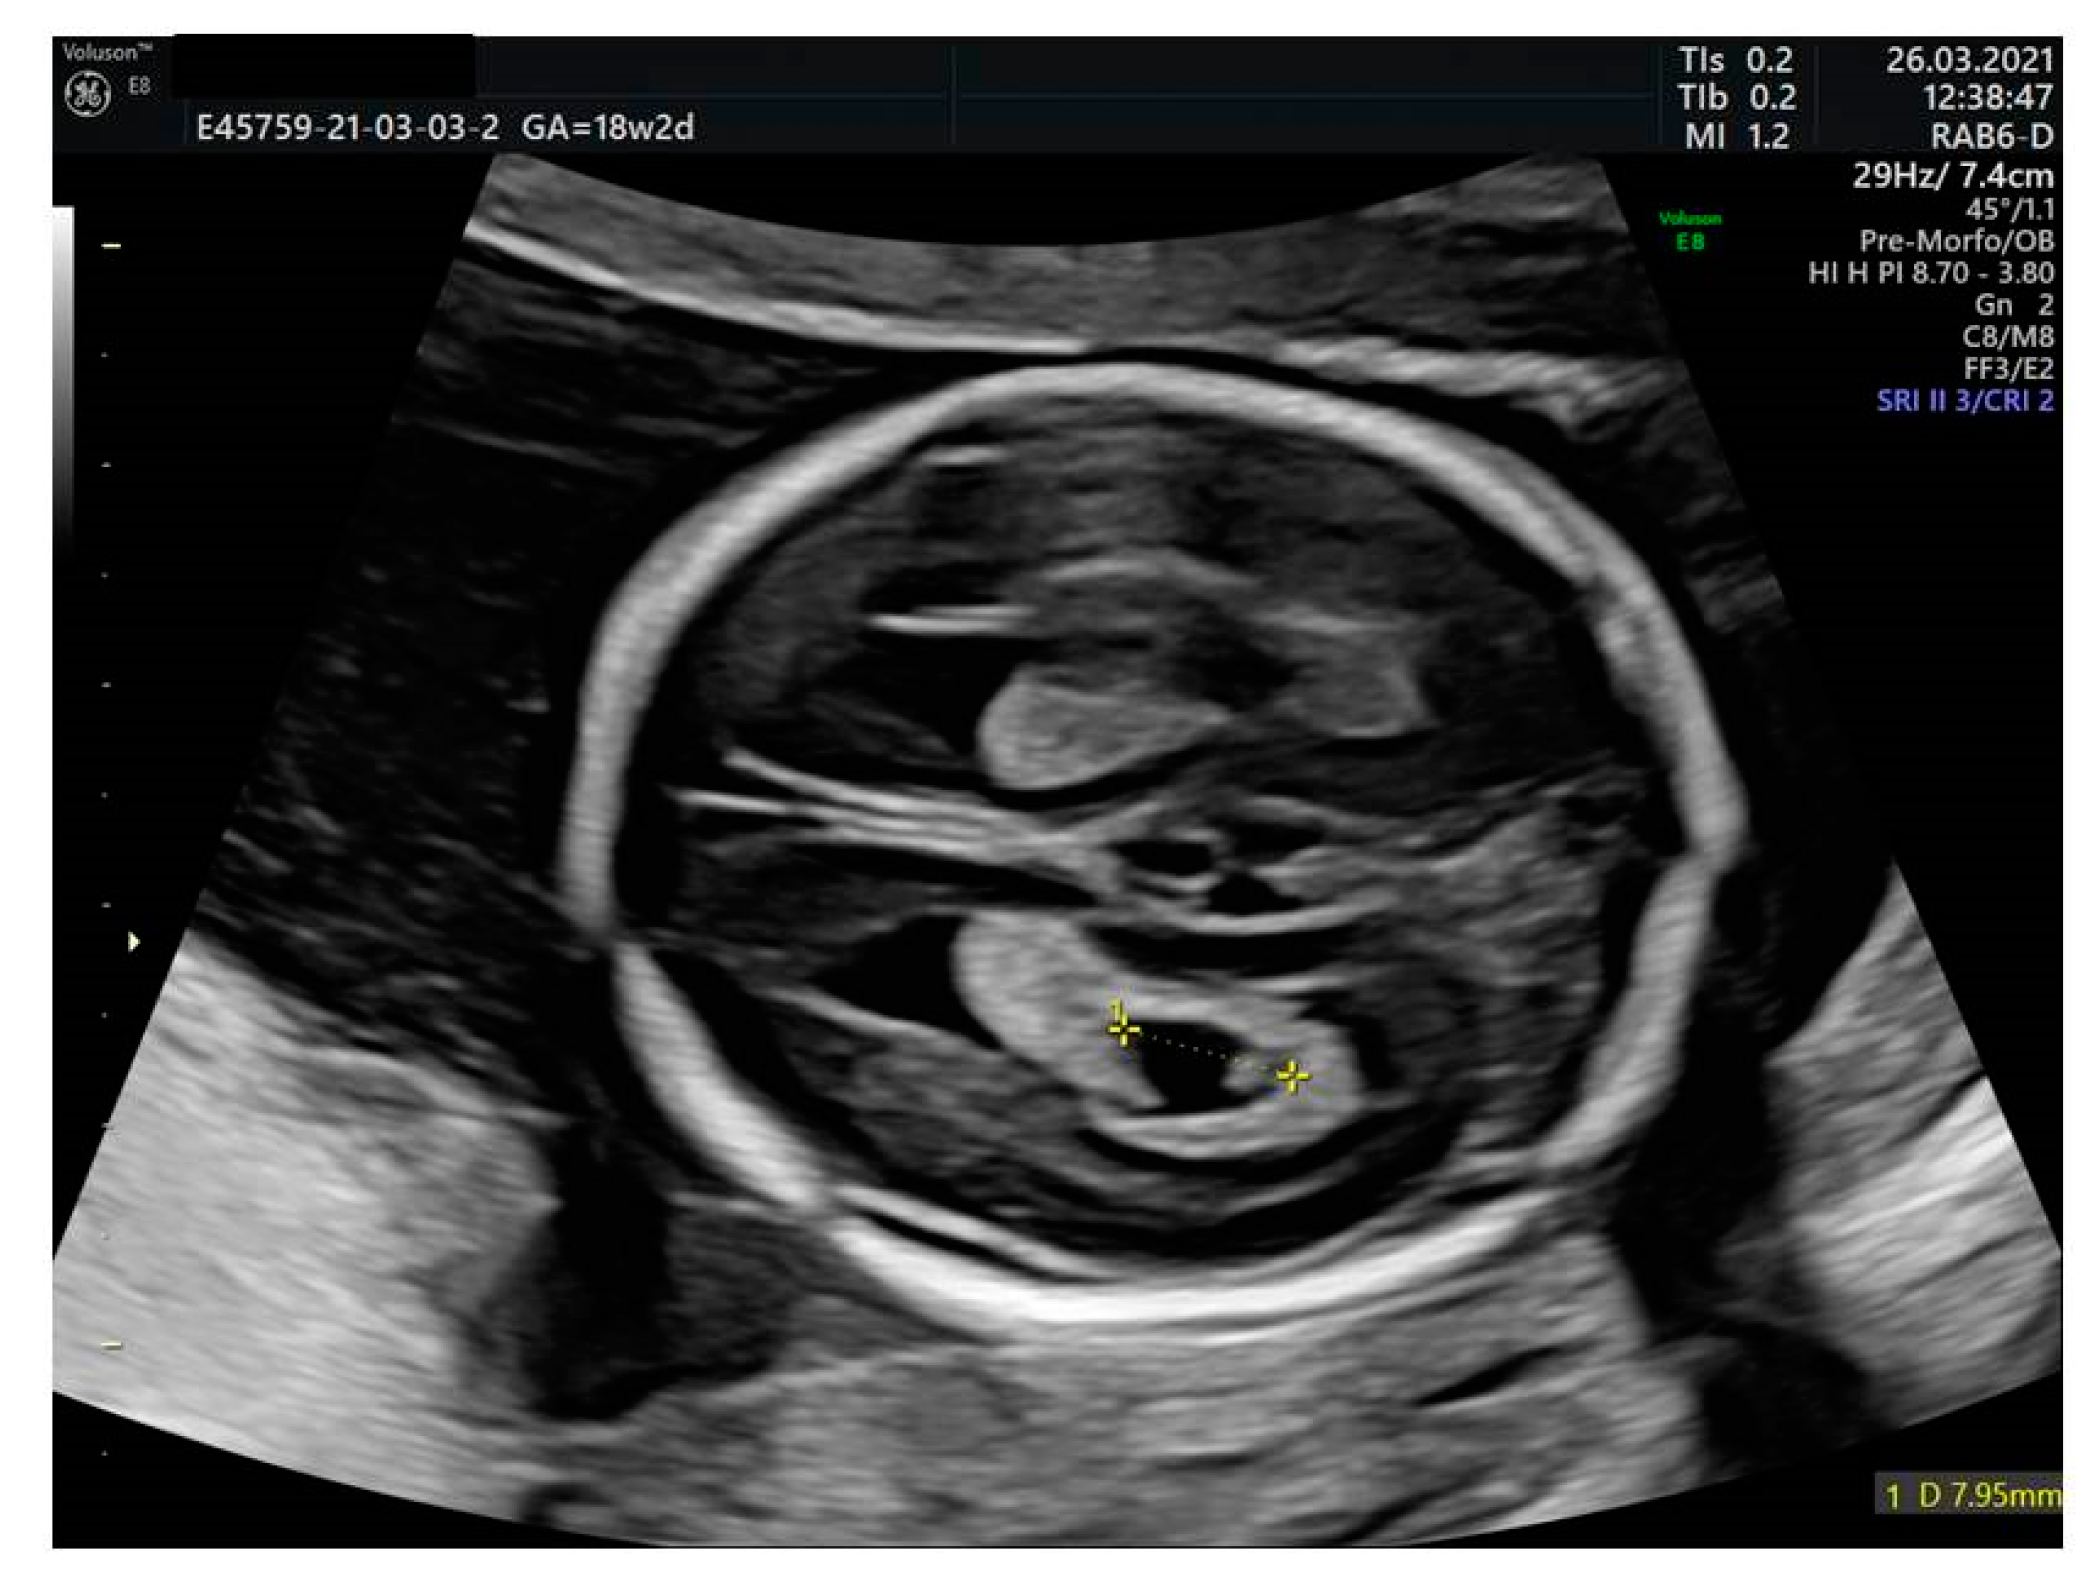

| Mild to moderate ventriculomegaly (VM) | Measured in an axial transventricular plane at the atrium of the posterior horn with calipers placed over the inner edges [31]. Ventriculomegaly is categorized as mild between 10 and 11.9 mm), moderate between 12 and 14.9 mm [31]. |